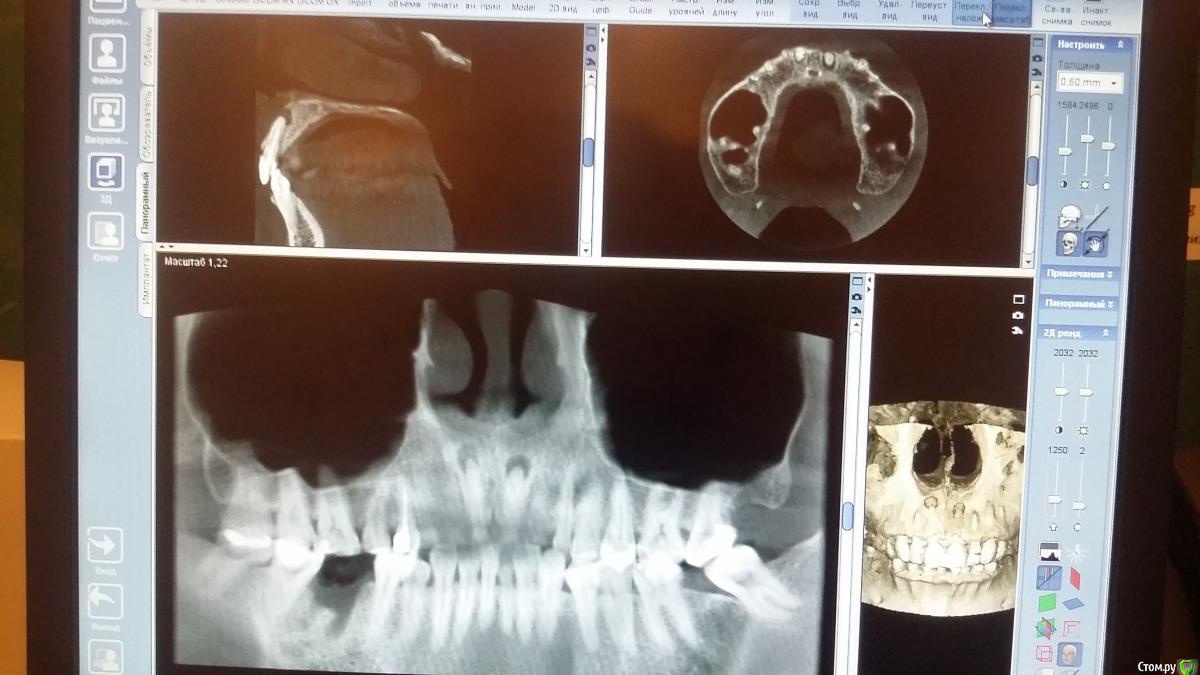

Recive Опубликовано 5 февраля, 2015 Поделиться Опубликовано 5 февраля, 2015 Анамнез: ранее лечены были, лет 5 назад.жалоб нету.сделали кт перед импл. Обнаружил тАкое!объективно: свищевой ход от зуба 1.2 лечение: ревизия кк в канал по апекс (да так, чтоб из ушей пошел) септомиксин (до момента появления его из свищевого хода)следующее посещение через неделю,.повторная ммо + замена на каласепт.мысли: её терапевтически не выличить, думаю на резекцию отправлять. Вопрос на какой стадии на резекцию?Чем пломбировать кк перед резекцией? Ссылка на комментарий

Бобр Опубликовано 5 февраля, 2015 Поделиться Опубликовано 5 февраля, 2015 У вас есть Клкт прекрасно, вы можете по нему определить степень резорбции корней. Определитесь где там апекс. За апекс ничего не выводите. Септомиксин на мой взгляд не обязателен. Резекция вполне тоже не понадобится. Тщательное и очень аккуратное эндо по всем правилам Ссылка на комментарий

Recive Опубликовано 6 февраля, 2015 Автор Поделиться Опубликовано 6 февраля, 2015 У вас есть Клкт прекрасно, вы можете по нему определить степень резорбции корней. Определитесь где там апекс. За апекс ничего не выводите. Септомиксин на мой взгляд не обязателен. Резекция вполне тоже не понадобится. Тщательное и очень аккуратное эндо по всем правилам Как определить степень резорбции корней? Могу на неделе di comments Кт выложить.если необходимо Ссылка на комментарий